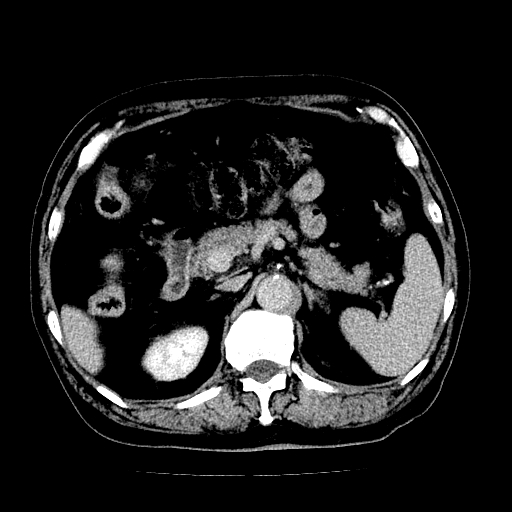

男,71岁,皮肤黄染四天。

考虑胆总管癌并肝内外胆管扩张。

支持考虑胆总管癌并肝内外胆管扩张。 局部应薄扫。心包钙化。

胰腺上端胆总管内见软组织影,强化不明显,结合临床,还是考虑低位梗阻性黄疸,胆总管癌可能性大